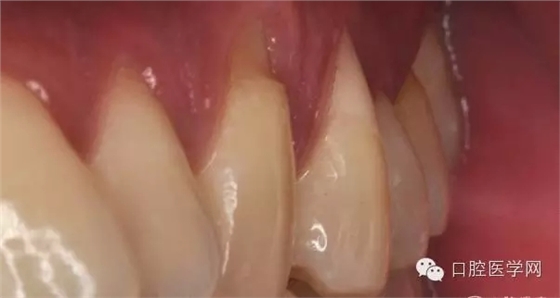

(通過以上圖片我們可以看到患者的3-4號牙齒出現(xiàn)楔狀缺損引起明顯的牙齦萎縮,這時我們第一步需要找出楔損的直接因素。可導(dǎo)致楔狀缺損的因素我就不多說了,我們做根面覆蓋時最需要排除的是:是否有牙合、創(chuàng)傷情況出現(xiàn))

(患者的3號牙有缺損但無充填物 4號牙有明顯缺損并有樹脂充填物)